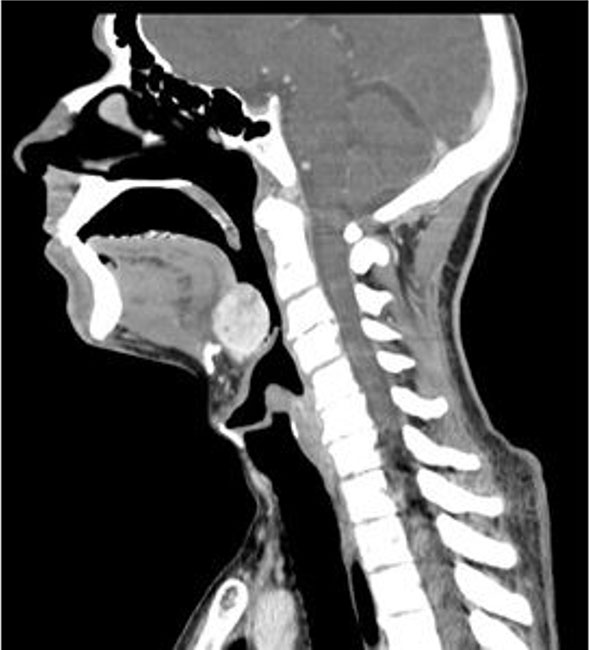

Computed tomography scan documented a non-homogeneously hyperdense structure with an oval morphology of 25 mm with a craniocaudal extension of 29 mm that is located behind the base of the tongue and above the hyoid bone and the epiglottis with which it contracts continuity. No thyroid was appreciable in its normal anatomical location (Figure 2).

Figure 2: CT scan of the lesion.